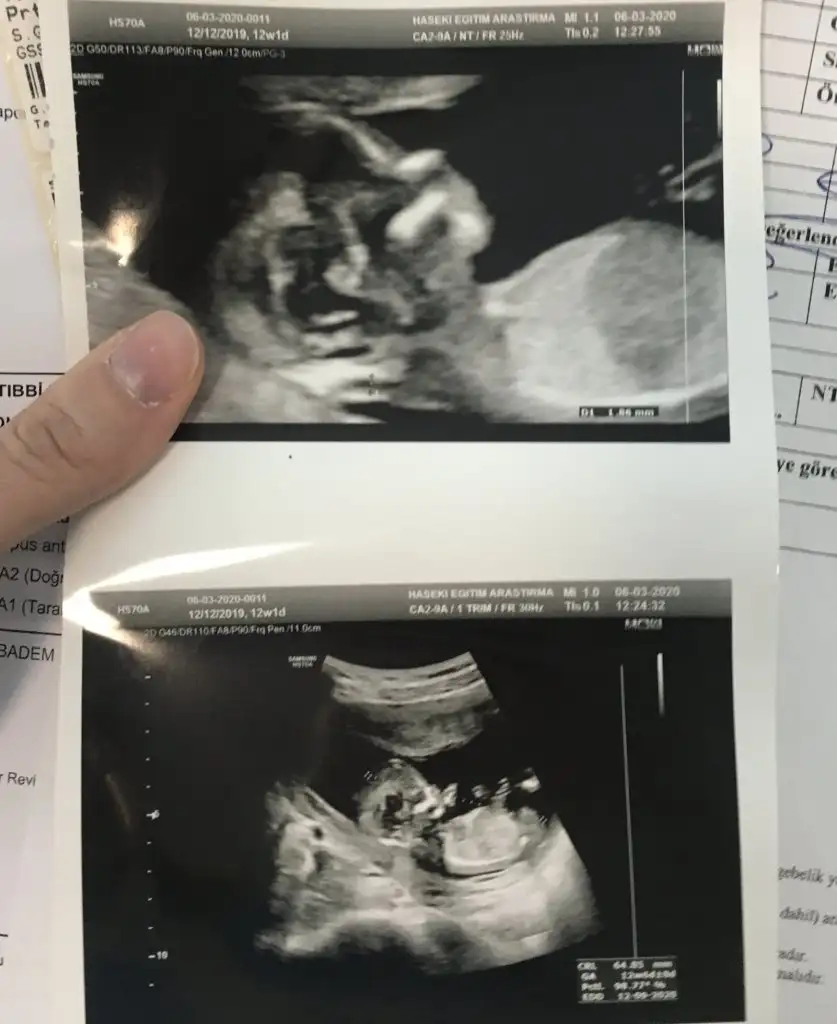

Erkek gibi 12+ yada 13 hafta paylaşınIkra meyra yorumunuzu alabilir miyim![]()

Tmm o zaman kontrole gidersek paylaşırım inşallahErkek gibi 12+ yada 13 hafta paylaşın

M mely15 bi bakarmısın canım ben tahmin ettim arkadaşa sen ne diyorsun 12+4 usgKızlar kızlarvideodan ekran görüntüsü aldığım 2 fotoğrafta nub birinde paralel birinde dik duruyor hareket ettiği sırada değişiyor olabilir mi

Ikra meyra Eki Görüntüle 2601535 Eki Görüntüle 2601536